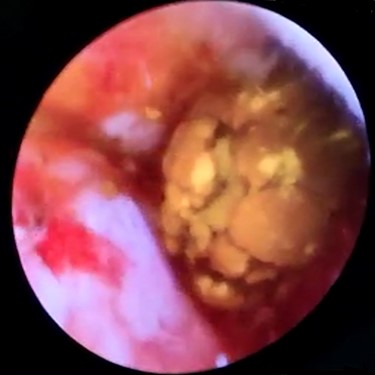

Another 5 mm epigastric trocar was placed and cystic duct was dilated with silicone Bougies. Because of unavailable laparoscopic choledochoscope, a 3.1 mm Innovex® flexible ureterorenoscope was employed to perform a trans-cystic LCBDE.

In context of purulent cholangitis, a 10 mm stone was reached (Fig. 4) and extracted with Dormia basket under direct vision (Fig. 5). Furthermore, control choledochoscopy and cholangiography did not show any other stones in the CBD and contrast easily passed into the duodenum (Fig. 6).